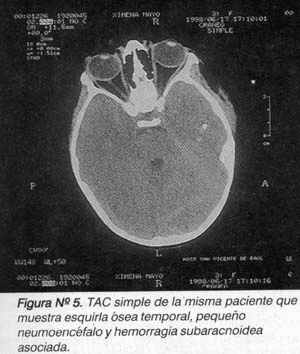

Los estudios imagenológicos al momento del ingreso revelaron fracturas y esquirlas en la mayoría de los casos y solo en 2 casos se evidencio la presencia de hematomas significativos, uno de ellos extradural y otro subdural. Vale la pena anotar que solo se revisaron 23 tomografías ya que algunas no se encontraron a los pacientes fueron intervenidos con base en una placa de rayos X (Figura No. 4 y 5).